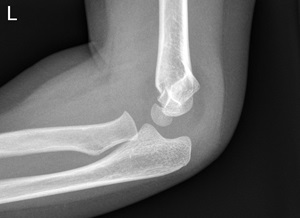

Displaced supracondylar fracture with an intact posterior cortex (Gartland type 2)

- Discuss with ED Consultant or Orthopaedic team regarding possible treatment

- High collar and cuff

- High collar and cuff and re-X-ray

- Admission for manipulation under anaesthetic (MUA)

- Application of a high collar and cuff uses the triceps to reduced posterior angulation of the fracture.

- Consider analgesia / sedation such as Intranasal Fentanyl and / or Nitrous Oxide / Oxygen (50:50): Self Demand – Clinical Practice Manual (internal WA Health only).

- Check radial pulse post application.

Supracondylar fracture with posterior angulation